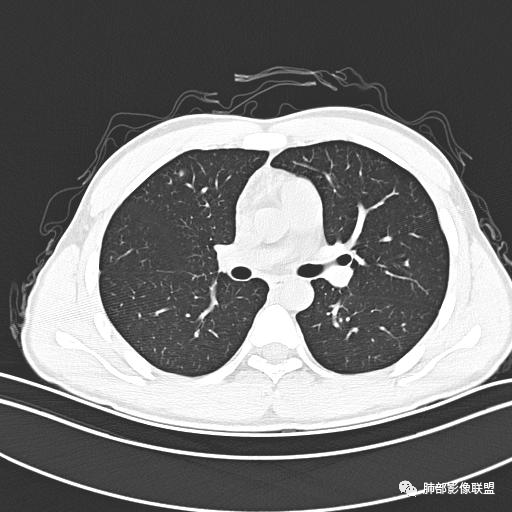

小强:青年,发热,皮疹;双肺散在结节,周围磨玻璃,点晕征,疱疹病毒感染,鉴别荚膜组织胞浆菌,结核。 大雄:青年,急性起病,发热伴全身皮疹2天,抗病毒治疗体温有下降。双肺随机分布大小不等类圆结节,“点晕征”。考虑水痘-疱疹病毒(VZV)血播询问接触史,查体皮疹分布以及形态基本可诊断。 王开金江津中心医院呼吸科:青年男性,起病急,病程短,以发热,皮疹为首发症状,感染指标以单核细胞升高为主,胸部ct双肺多发结界,周围有晕,点晕表现,随机分布,同意於老师意见,水痘疱疹病毒血流感染累及肺。 王秀仙:双肺多发大小不等结节,周围有晕,边缘模糊,呈点晕征表现。青年,急性起病,发热伴全身皮疹2天,抗病毒治疗体温有下降。考虑疱疹病毒。鉴别荚膜组织胞浆菌。 傅昌瑜:19岁男性,发热、全身皮疹2天,单核细胞增高,双肺多发结节,结节边缘见边界不清磨玻璃影。点晕征+发热、全身皮疹+单核细胞增高——考虑水痘-带状疱疹病毒肺炎。 一切∮随缘:年轻男性,发热,皮疹两天,实验室,CRP,PCT增高,影像:双肺多发散在磨玻璃结节,边界欠清,大小不等,呈点晕征改变,以血管束周围分布为主,局部血管束略增粗,其它无明显改变,考虑:1:病毒性肺炎(水痘疱疹病毒?不知道皮肤有无改变)2:真菌(组织胞浆菌,血管侵袭性肺曲霉)3:GPA4:寄生虫(实验室没有看到嗜酸细胞增高) 赵山河:双肺散在结节,周围有晕,边缘模糊,呈点晕征表现。青年,急性起病,发热伴全身皮疹2天,抗病毒治疗体温有下降。考虑水痘—疱疹病毒感染。洪桥爱:青年男性,发热、皮疹2天,伴瘙痒,皮疹于面部首发,之后进展至全身,虽然没有对皮疹进行描述,但是从出疹时间及皮疹进展情况,伴瘙痒,应该就是个水痘患者;CT提示双肺随机分布结节影,部分结节伴有边界不清晕征,考虑水痘血播肺。 刘强:年轻男性,急性起病,皮疹,发热,抗感染治疗体温下降,说明有效。影像表现为散在点晕征,感染类疾病谱(疱疹病毒,真菌,结核),结合年龄,皮肤皮疹,考虑水痘-疱疹病毒性肺炎。 小兜:男性,19岁,发热皮疹两天,颜面部至全身,CRP,降钙素及单核增高。CT示双肺散在小结节,周围伴磨玻璃影,点晕征,考虑为水痘-带状疱疹病毒(varicella-zoster virus,VZV)肺炎 必有路:青年,皮疹+发热+“点晕征”→水痘-疱疹病毒(VZV) 许慧良:青年男性患者,发热、皮疹2天,体温最高38.5℃,第3天皮疹扩展至全身,伴瘙痒,胸部CT:双肺多发随机分布的小结节,结节周边见边界模糊的晕征,考虑水痘病毒感染流心明智:男,19,急性起病,发热伴全身皮疹2天。出疹顺序头→全身,抗病毒有效。胸部CT:两肺多发大小不等类圆形实性小结节影,随机分布,结节周围环绕GGO,边界模糊,呈点晕征。出疹特点是关键,未提示。考虑:血播病毒性肺炎,水痘-疱疹病毒?麻疹?鉴别荚膜组织胞浆菌、TB、血管炎、寄生虫等。 浪迹天涯:病灶多为5-10mm大小结节,结节周围可见磨玻璃样的晕环,常多发,可分布于肺内任何区域,考虑水痘—带状疱疹病肺炎如果短时间内有新的一个区域浸润,更加能说明,